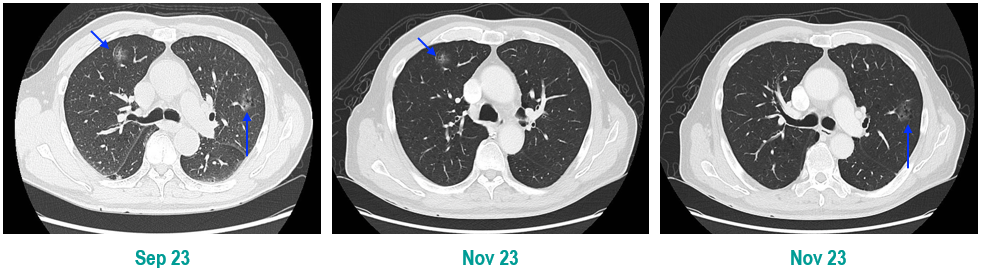

PET-CT(2023年9月):右下肺叶发现6.9×6.7×6.6cm的FDG高摄取肿块,伴右侧第7、8肋骨侵犯可疑,右肺门淋巴结肿大,双肺上叶多发结节,考虑腺癌谱系疾病。

CT及PET-CT随访(2023年11月、2024年1月):评估新辅助治疗效果,右下肺叶肿块缩小,右肺门淋巴结代谢活性消失,右肺上叶结节稳定但代谢活性降低,左肺上叶及双侧磨玻璃样病变稳定。